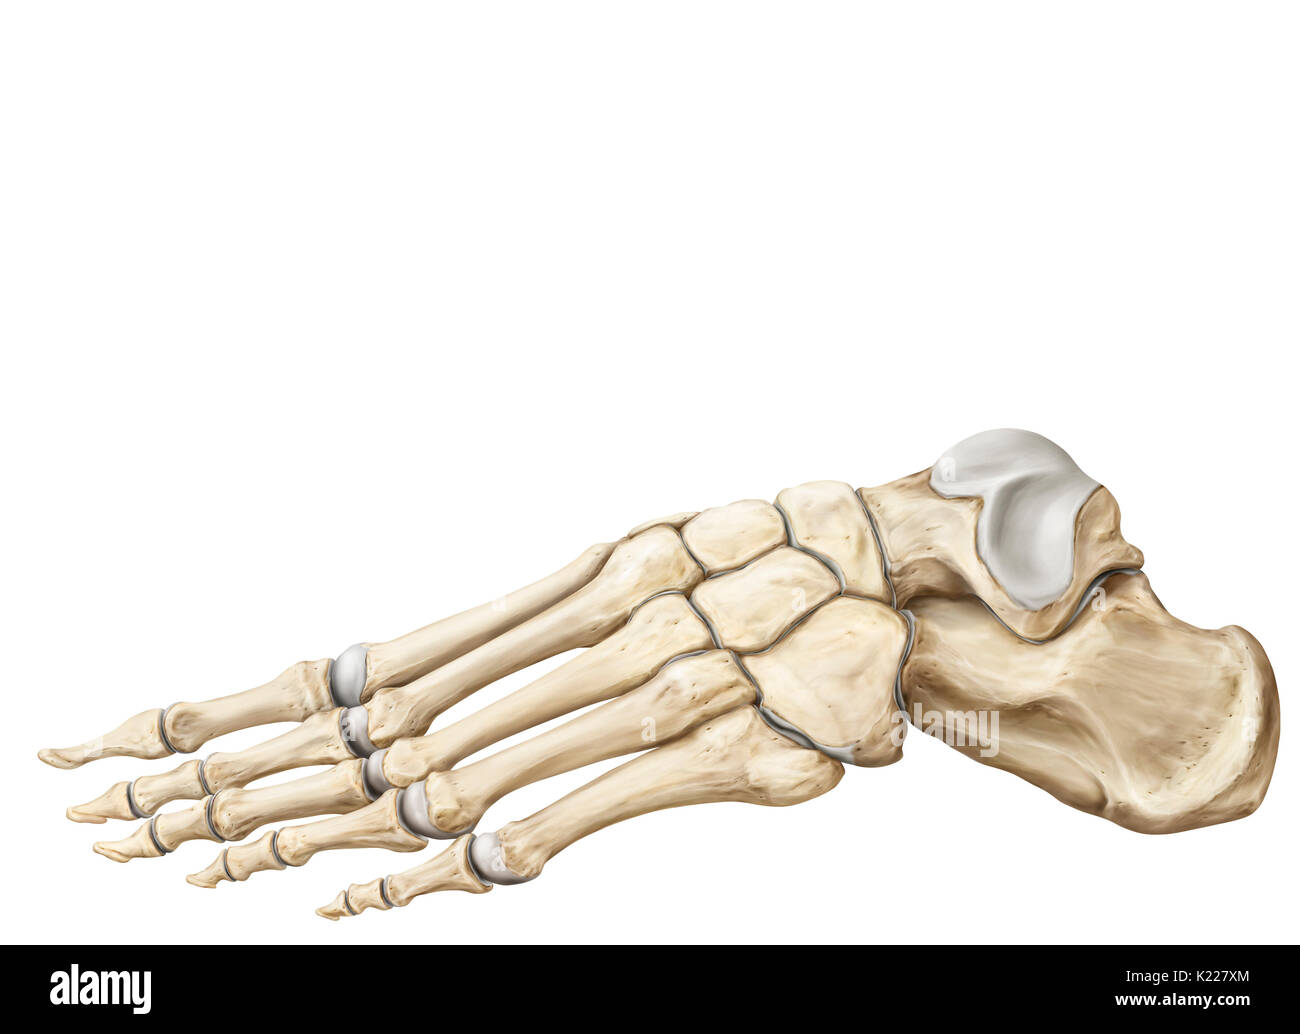

RMK228DY–Partie terminale du membre inférieur, reposant sur le sol au cours de posture droite ; le squelette du pied a 26 os.

RMK227XM–Partie terminale du membre inférieur, reposant sur le sol au cours de posture droite ; le squelette du pied a 26 os.